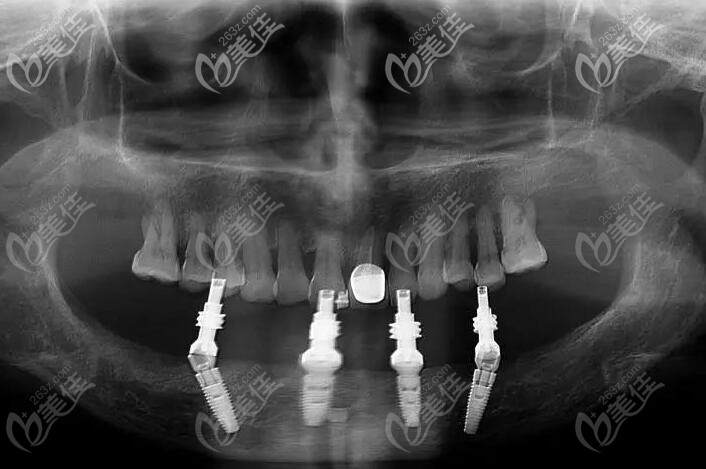

下半口用allon4種植的CT照片▼

下半口用allon4種植的CT照片